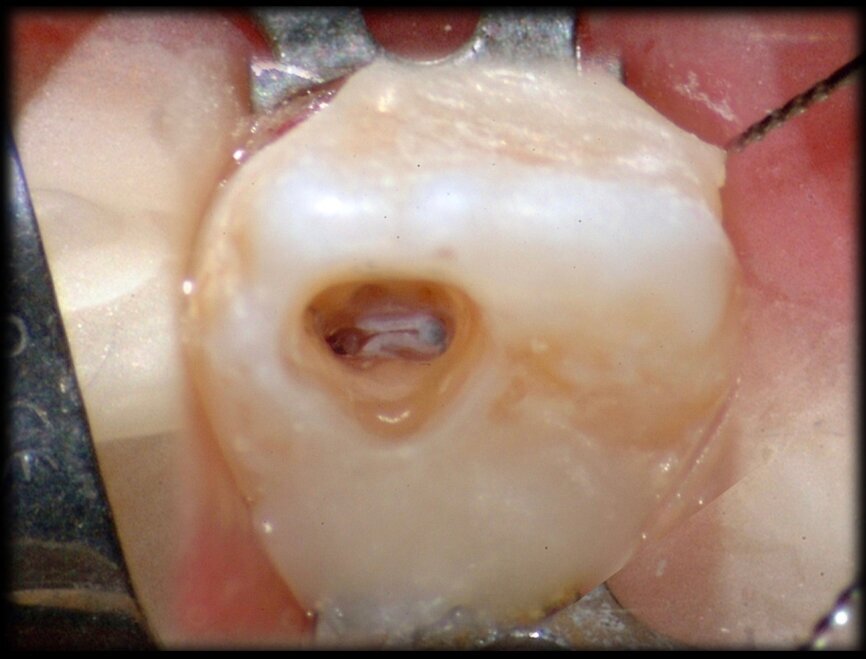

Another compelling advantage of this 3D technology is the possibility of using a minimally invasive approach for performing cavity access. For demonstration, the next case involves a dens in dente. The CBCT scan shows a separation between the two canal systems of the canine and the decay involves the portion of tooth where the dens in dente is present. The treatment plan therefore involved root canal therapy for just one portion of the pulp, while the other was to be kept vital. The image sequence of the treatment shows how it was possible, using CBCT and a surgical microscope, to perform a minimally invasive access, which spared much of the canine’s clinical crown and kept the disease-free portion of the tooth vital. The radiographic follow-up confirmed complete healing of the lesion and the vital part of the canine did not present any signs of disease six years later (Figs. 32–37).